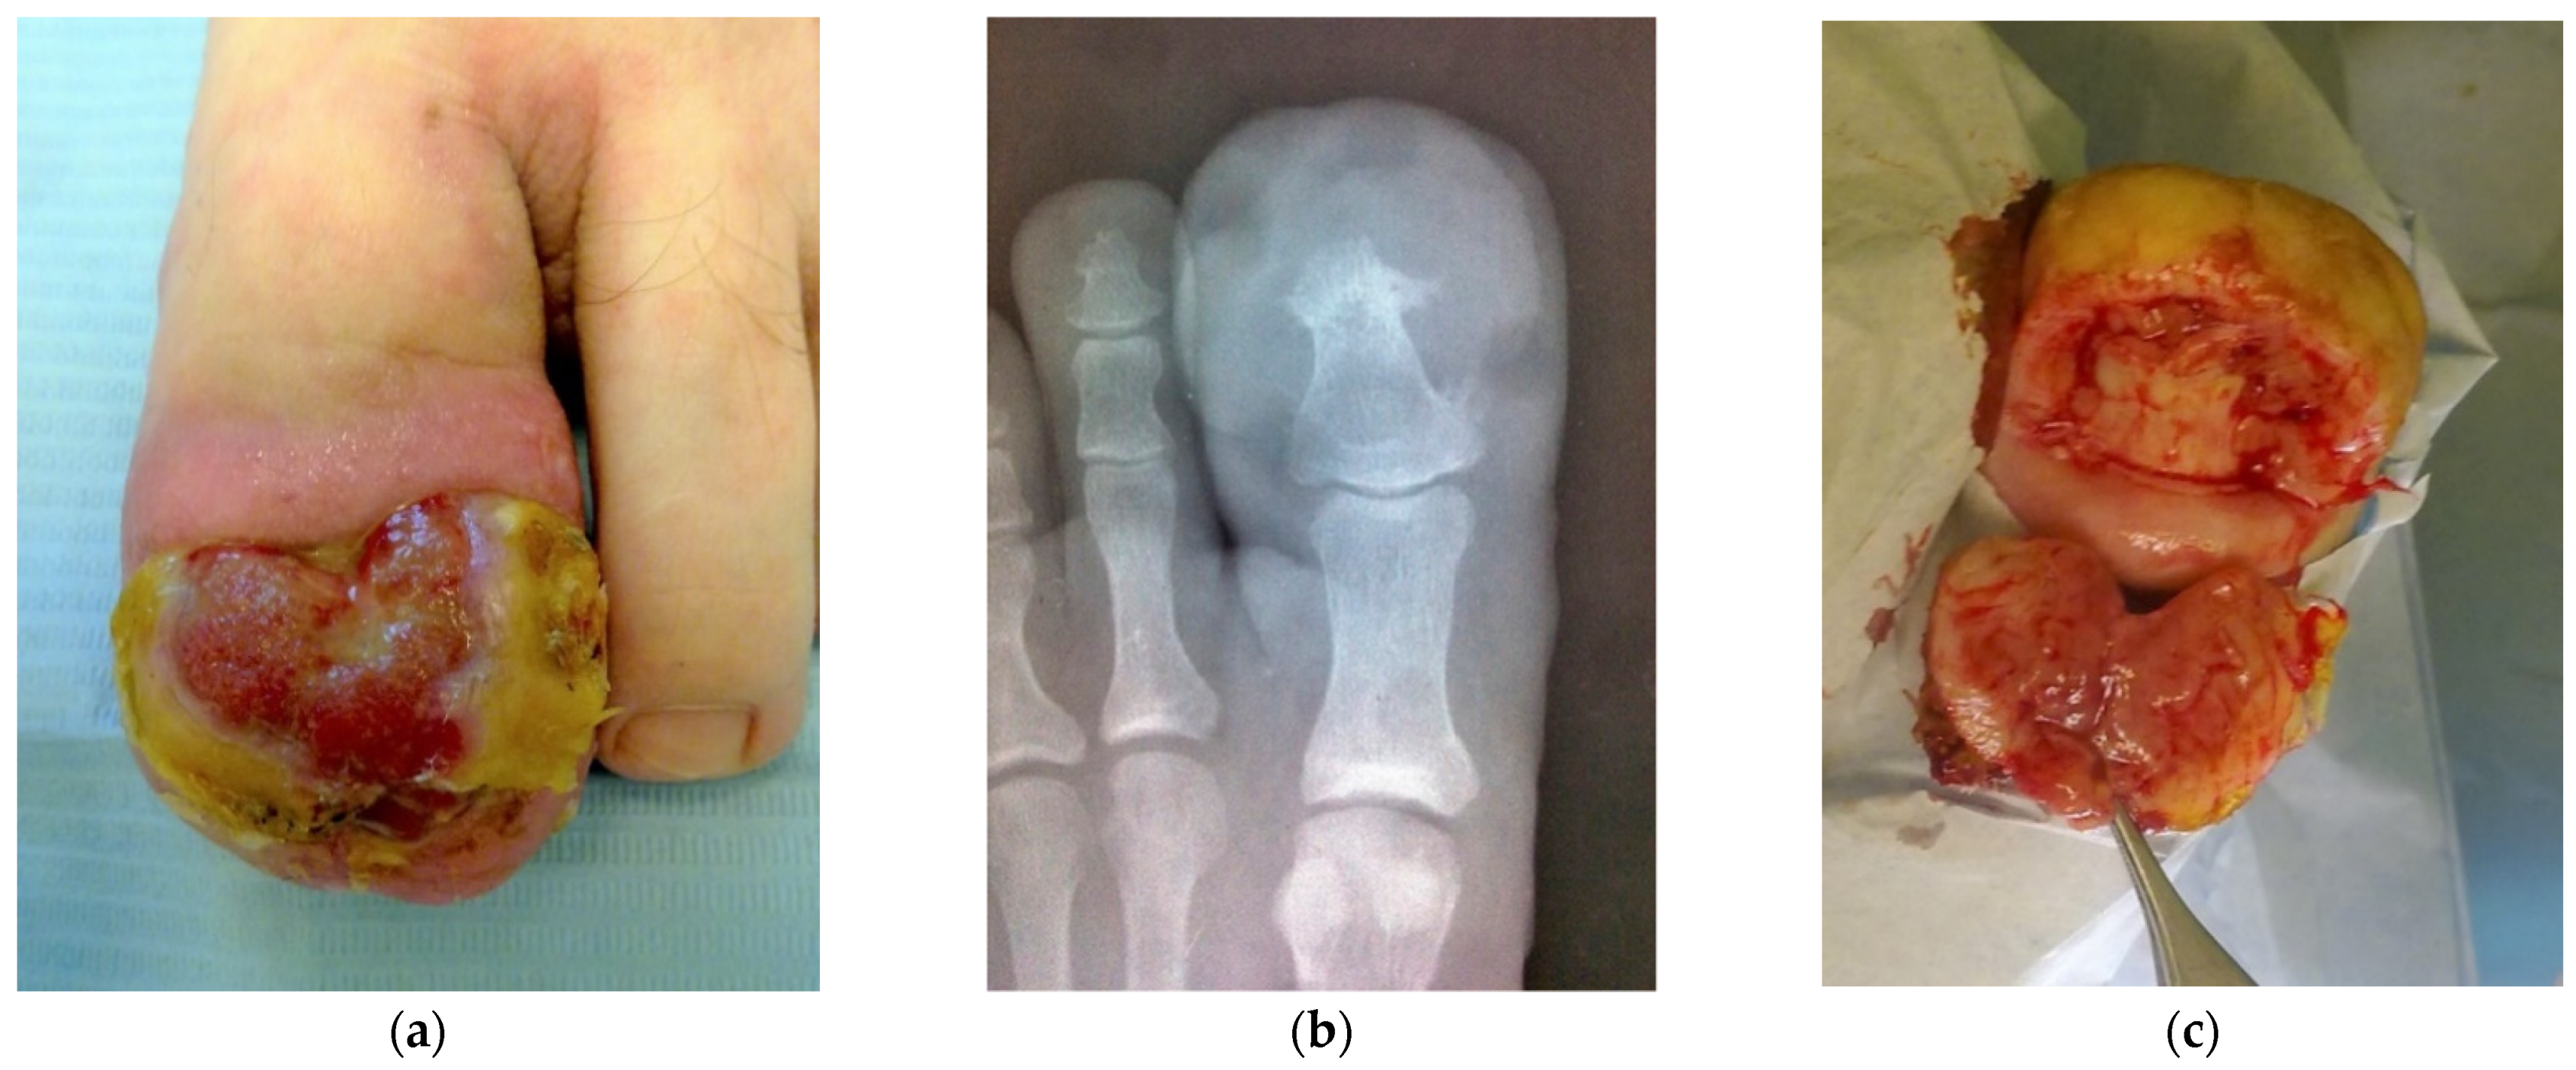

Large Lobular Capillary Hemangioma Associated with Ingrown Toenail: Histopathological Features and Case Report

2. Case Report